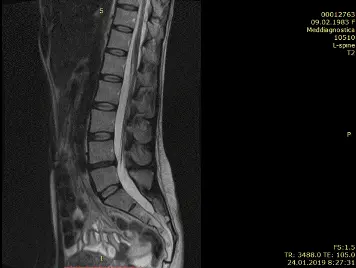

Бывают случаи, когда вправление грыжи можно провести за несколько сеансов. Иногда даже за один. Это возможно при протрузии диска и грыже небольшого размера. Если же грыжа большая и сопровождается болью в ноге, то для излечения понадобится курс лечения. Как это было с одной из наших многочисленных пациентов Ириной, результаты чего видны на МРТ, что ниже.